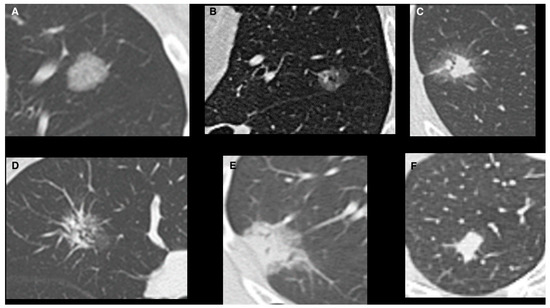

| Pure GGO, n (%) | 162 (42%) | 108 (67%) | 54 (24%) | <0.0001 |

| Pure GGO | 3.3 | 2.9–4.5 | 0.01 |

| Pure GGO | 2.3 | 2.8–4.8 | 0.003 |